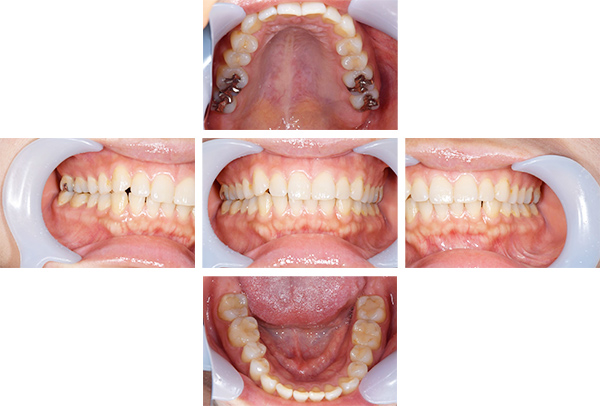

インレー症例

治療前

治療後

治療期間 8回(2ヶ月)

費用 ・セラミックインレー9本

合計:495,000円

治療リスク・副作用 ・詰め物、被せ物をする時は自分の歯を削ることになります

・歯ぎしり・食いしばりが強い方は、セラミックが割れてしまうことがあります。